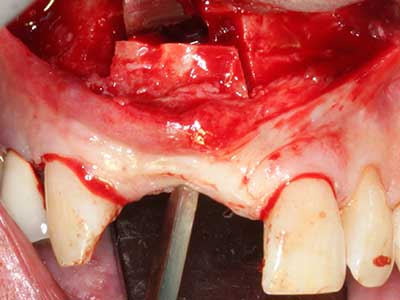

En la extracción de bloques óseos la piezocirugía también presenta ventajas adicionales: Además de la alta precisión en la osteotomía que ya se ha descrito antes, se ha comprobado que el uso de los delgados insertos de sierra resulta especialmente cuidadosas con el hueso. Frente a esto, sobre todo cuando se usan las fresas de Lindemann, cabe esperar pérdidas en la extracción significativamente más altas debido al mayor grosor de la parte frontal del cabezal (Lakshmiganthan, Gokulanathan et al. 2012). La separación basal que se necesita en particular en los injertos de bloque extraídos de forma retromolar se ve facilitada mediante sierras perpendiculares especialmente previstas a tal fin, lo que permite considerar que la cirugía piezoeléctrica es un procedimiento preciso y seguro para la obtención de bloques de hueso en el área retromolar (Happe 2007) (fig. 1-12).